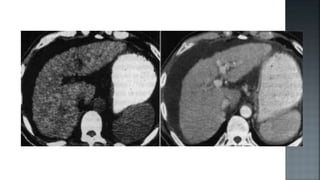

 Permite establecer el diagnostico con certeza.

 Puede ser realizada por vía percutánea o laparoscópica.